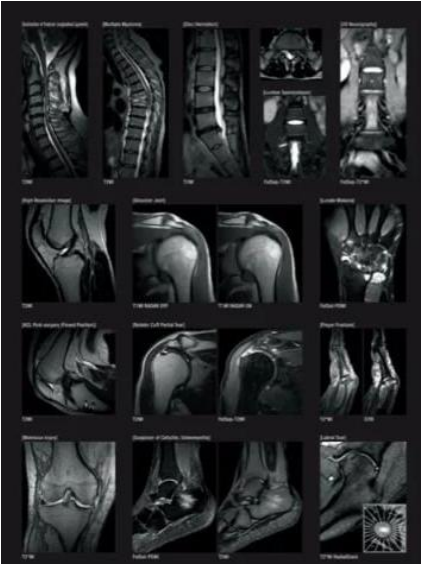

日常生活中の心電図を記録することで、通常の検査では見つかりにくい異常も調べることができます。 - レントゲン・CT・MRIなどの画像検査

頭部・胸部・腹部をはじめ、内臓や血管、骨の状態を画像で詳しく確認します。

当院では、短時間・低負担での撮影が可能なCTや、放射線を使用しないオープンMRIを利用し、必要に応じて隣接医療機関の高度な検査機器も共同で使用しています。 - 超音波検査(エコー)

日立製オープンMRI(APERTO Lucent 0.4T)

MRI 装置は磁力を用いており、放射線を使用しないため人体への影響がなく、あらゆる方向の断面を画像化することができます。また、オープンMRIは広く開放した環境で検査が受けられるので圧迫感が少なく、狭いところが苦手な方や小児の方にも安心して検査をお受けいただけます。